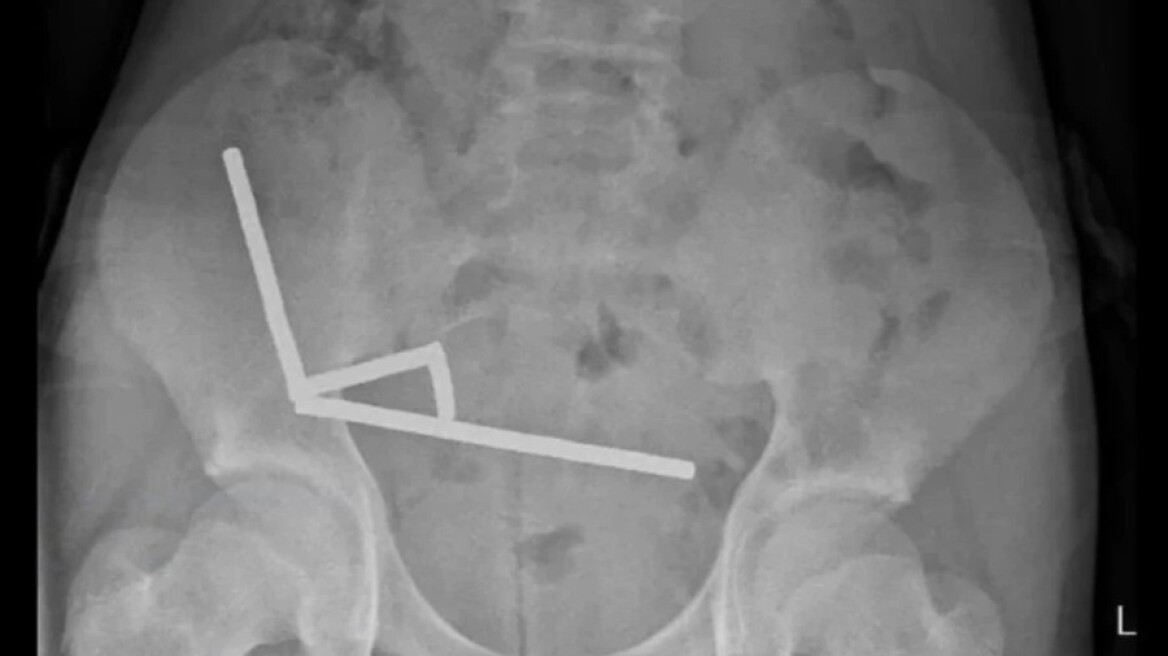

Εκεί οι γιατροί διαπίστωσαν ότι είχε καταπιεί περίπου 80 με 100 μαγνήτες νεοδυμίου διαστάσεων 5 επί 2 χιλιοστών περίπου μία εβδομάδα νωρίτερα, ανέφερε έκθεση του νοσοκομείου στο New Zealand Medical Journal.

Η ακτινογραφία έδειξε ότι οι μαγνήτες είχαν συσσωρευτεί σε τέσσερις ευθείες γραμμές μέσα στα έντερα του παιδιού. Βρίσκονταν σε ξεχωριστά μέρη του εντέρου και είχαν κολλήσει μεταξύ τους λόγω μαγνητικών δυνάμεων.